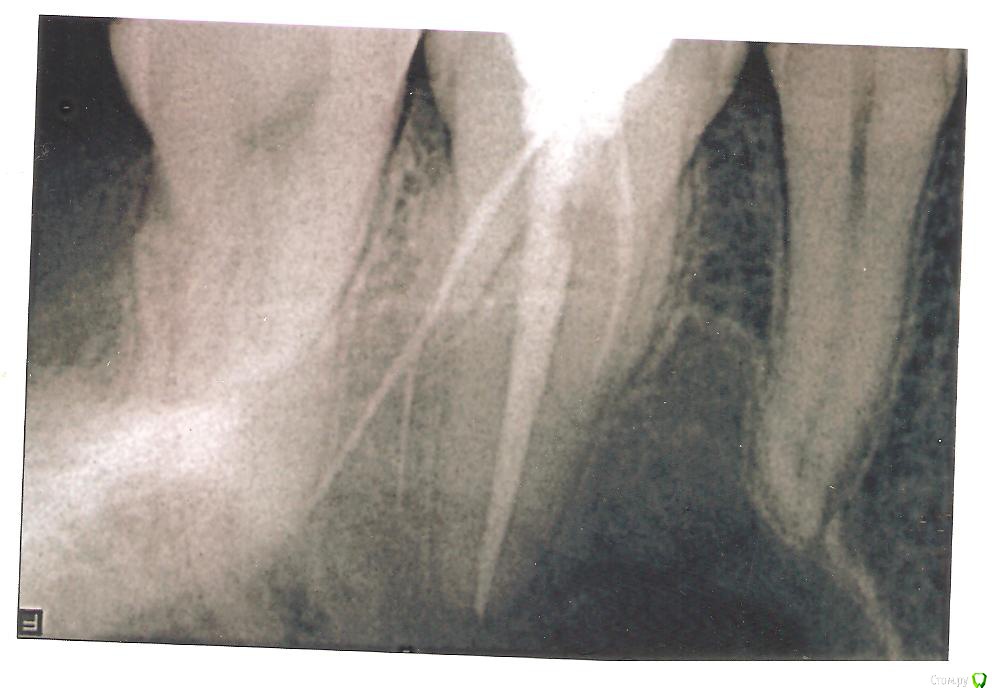

Vasyl Опубликовано 7 июня, 2015 Поделиться Опубликовано 7 июня, 2015 Мне 34 года. В марте 2015 провели лечение каналов в 26 зубе. До сих пор, со времени лечения, беспокоит небольшая боль при нажатии пальцем на 26 зуб. Сделали снимок 26 зуба, смотрите снимок в приложении. Оказалось что канал был запломбирован гуттаперчивым штифтом за пределы канала в кость. Помню когда лечили этот зуб, стоматолог сделал контрольный цифровой снимок. Я ещё тогда у неё спросил-Это вы мне инструмент оставили ? На что она сказала мне НЕТ. Попытаюсь к ней попасть на приём. Хотя кроме ругани от неё ничего не ожидаю. И я думаю, в таком не признается, будет говорить что боль от 28.01.06.2015 удалил 28 зуб. Удаление было простое. Иногда побаливает место удаления. Надеюсь вместе с 28 пройдёт и 26. Можно ли вытащить этот штифт и препломбировать канал под микроскопом ? А может сразу удалить, так как штифт уже не вытащишь ? А после удаления удастся ли убрать остатки штифта или как это теперь сделать ? Ссылка на комментарий

faity Опубликовано 8 июня, 2015 Поделиться Опубликовано 8 июня, 2015 это не инструмент, это гуттаперча. перед эндодонтией или удалением сделайте КТ.лишиться зуба всегда успеете 1 Ссылка на комментарий

Vasyl Опубликовано 8 июня, 2015 Автор Поделиться Опубликовано 8 июня, 2015 это не инструмент, это гуттаперча. перед эндодонтией или удалением сделайте КТ.лишиться зуба всегда успеетеПоговорил с одним стоматологом, не тот кто лечил. Сказал очень опасно лезть даже под микроскопом и удалять опасно-рядом гайморова пазуха. Сказал так пройдёт, пол города с такими ошибками гуляет и ничего. С таким гуттоперчевым штифтом можешь 1000 лет прожить и ничего а полезут-хуже сделают. Гуттоперча инертна. А ещё поинтересовался-где сделали такое, глаза у него на лоб полезли. Ссылка на комментарий

Vasyl Опубликовано 9 июня, 2015 Автор Поделиться Опубликовано 9 июня, 2015 Поговорил с врачом, лечивший каналы 26 го зуба. Сказала, что это гуттоперча вышла за каналы зуба. Лучше её не трогать и не вытаскивать. Зуб лучше не удалять. Вообще о нём забыть. Твёрдое не жевать. Воспаление возможно в случае общего ослабления иммунитета: грипп, ОРВИ и т.д. Ссылка на комментарий